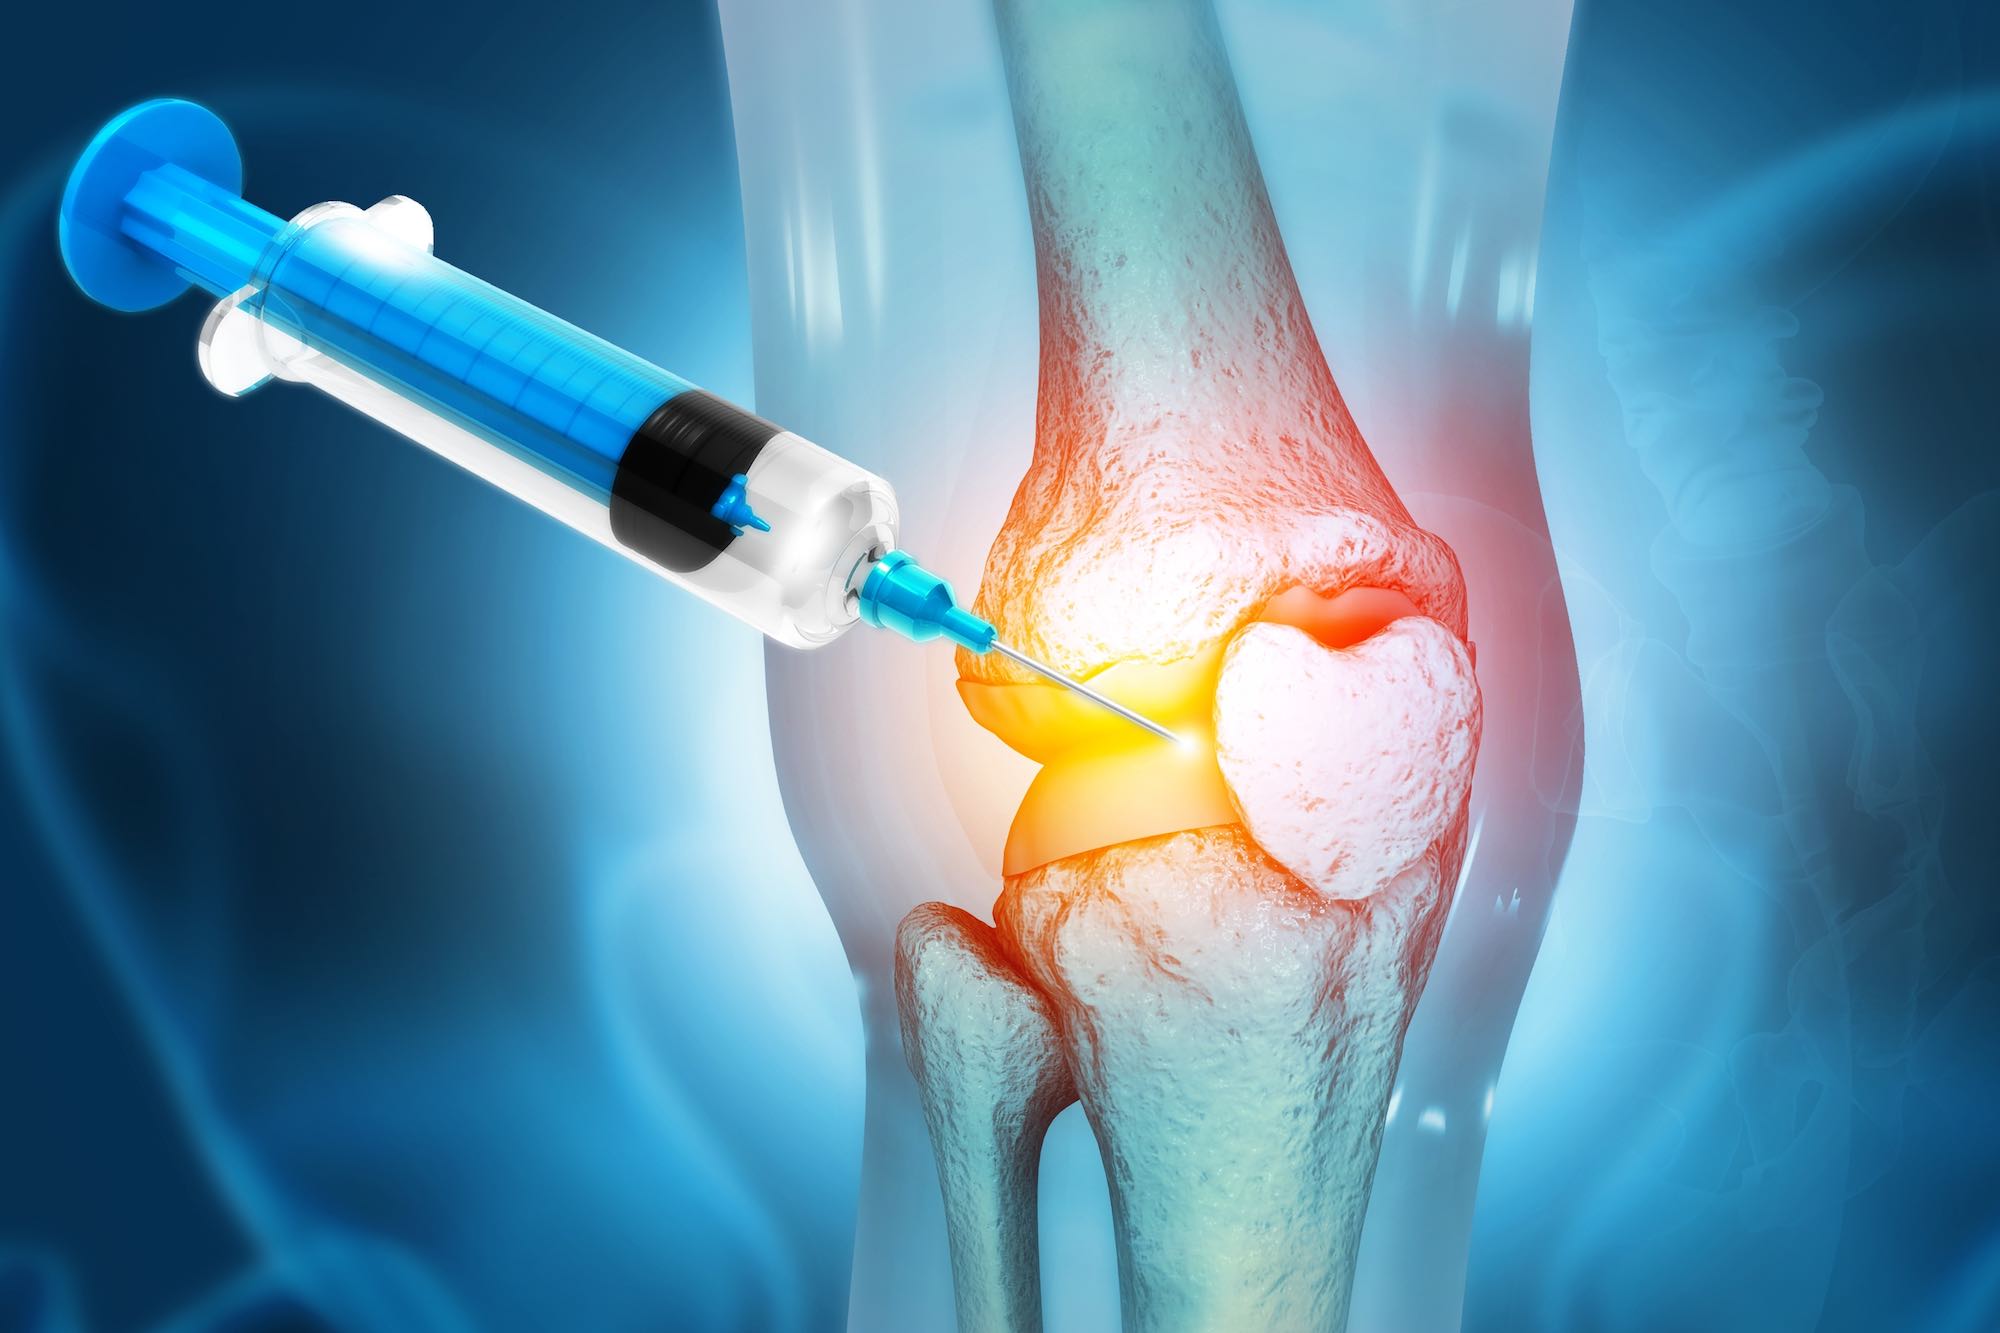

What Is Stem Cell Therapy Dr Amit Nathani MD

https://sbsportsmedicine.com/wp-content/uploads/2022/10/What-is-stem-cell-therapy.jpg